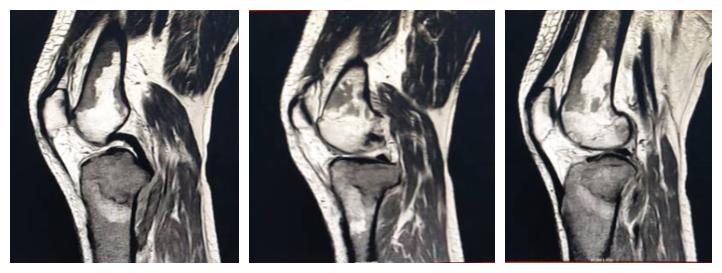

白血病关节病变:周某,男,71岁,既往白血病史,膝关节疼痛一月。

【eT2-TSE COR CLEAR 】

【eT2W-TSE SAG CLEAR】

影像所见:

关节腔及髌上囊见少量积液,左股骨下段及胫腓骨上段见片状异常影,边界尚清,呈地图形,T2WI呈稍低信号影。

【eT2W-SPAIR COR】

【eT2W SPAIR SAG】

【eT1W-TSE SAG CLRAR】

脂肪抑制序列胫骨上端见片状高信号影,信号不均。

【ePDW-TSE COR CLEAR】

内、外侧半月板前后角形态及信号正常,边缘规整,前后交叉韧带、内外侧副韧带及髌韧带形态及信号未见异常。

【T2WI-TSE-CLEAR】